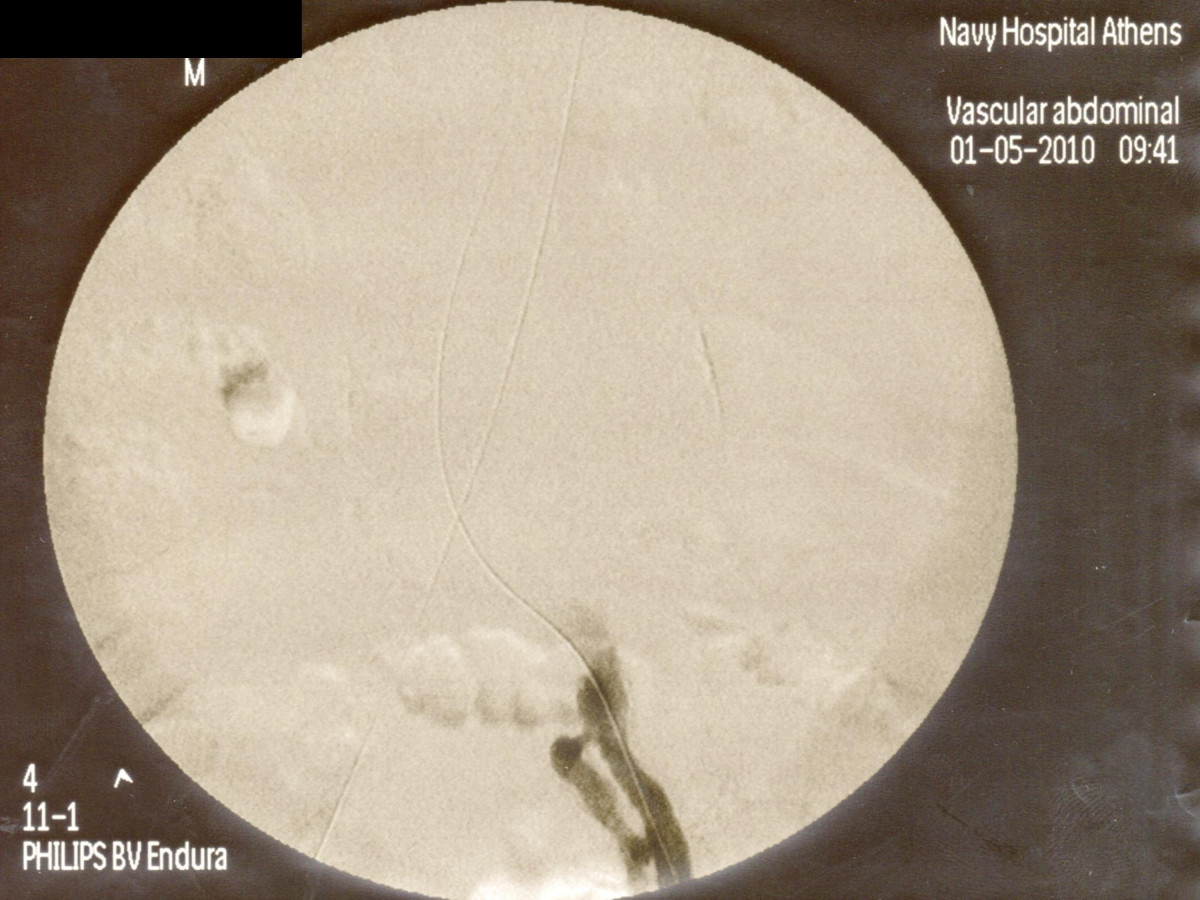

Ενδαγγειακή αποκατάσταση ανευρυσμάτων κοιλιακής αορτής

12ο Πανελλήνιο Συνέδριο Αγγειακής και Ενδαγγειακής Χειρουργικής

2010, Αθήνα